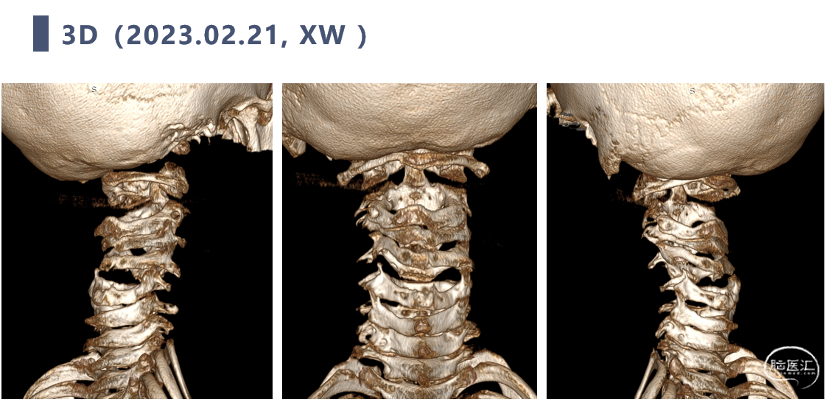

牵引治疗后复查CT

CT显示颈椎椎体最大深度只有8mm,枢椎椎弓根直径3.2mm

对于此种重度畸形的患者,术前牵引非常重要,为此我们首先选择HALO架牵引复位垂直脱位,患者可以自由活动,舒适度好。在牵引后期进一步行悬吊牵引,复位水平脱位。

双向牵引后,患者后方小关节仍存在一定绞锁,首先行后路手术,充分松解后方绞锁的关节突。再行前路手术,矫正后凸畸形,前路手术时因患者骨量极少,单纯前路螺钉复位力量弱,借助提拉工具完成良好复位。最后翻身行后路手术完成C2-7后路固定,因患者多数侧块发育异常,双侧C4-5无法置钉,应用椎板钩固定,双侧C2椎弓根直径只有3.2mm,但成功置入了两颗3.5mm螺钉。